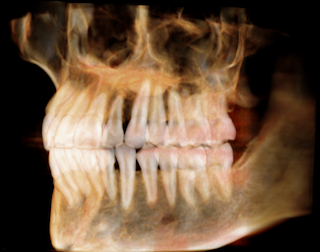

それには写真という目視の一瞬を記録するツールだけでは無く,骨の内部がどういう状況なのか,見えない歯の根の形状・方向,取り巻く骨の状態など外からは見えない部分も正確に把握する必要があります.

それを知るには1世紀以上以前からレントゲン写真によって可視可されてきました.

ただこのデジタル化は従来の現像プロセスが無くなっただけで(無論,画質は向上しましたが)人間の歯や上下の顎の骨という立体物を平面写真で観察・読影と言う部分に変わりはありませんでした.

そして2020年から当院はCBCTという歯科用CTスキャン機器を導入して歯科領域で必要な部分を立体的に観察できるようになりました.

こうして従来は平面化してしか観察出来なかった歯列全体を3Dとして立体的に観察する事が可能となりました.